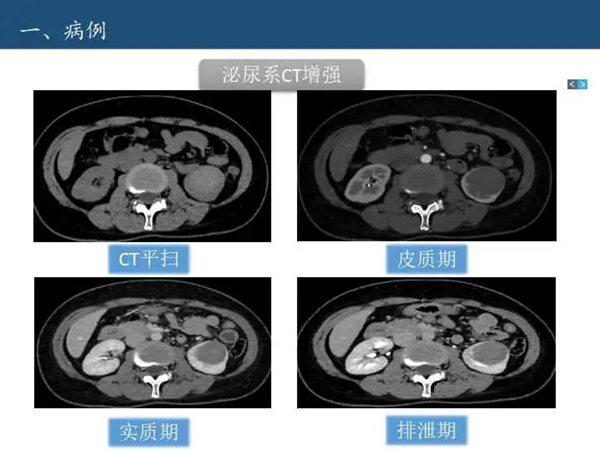

病例讨论—肾脏囊性病变Bosniak分级